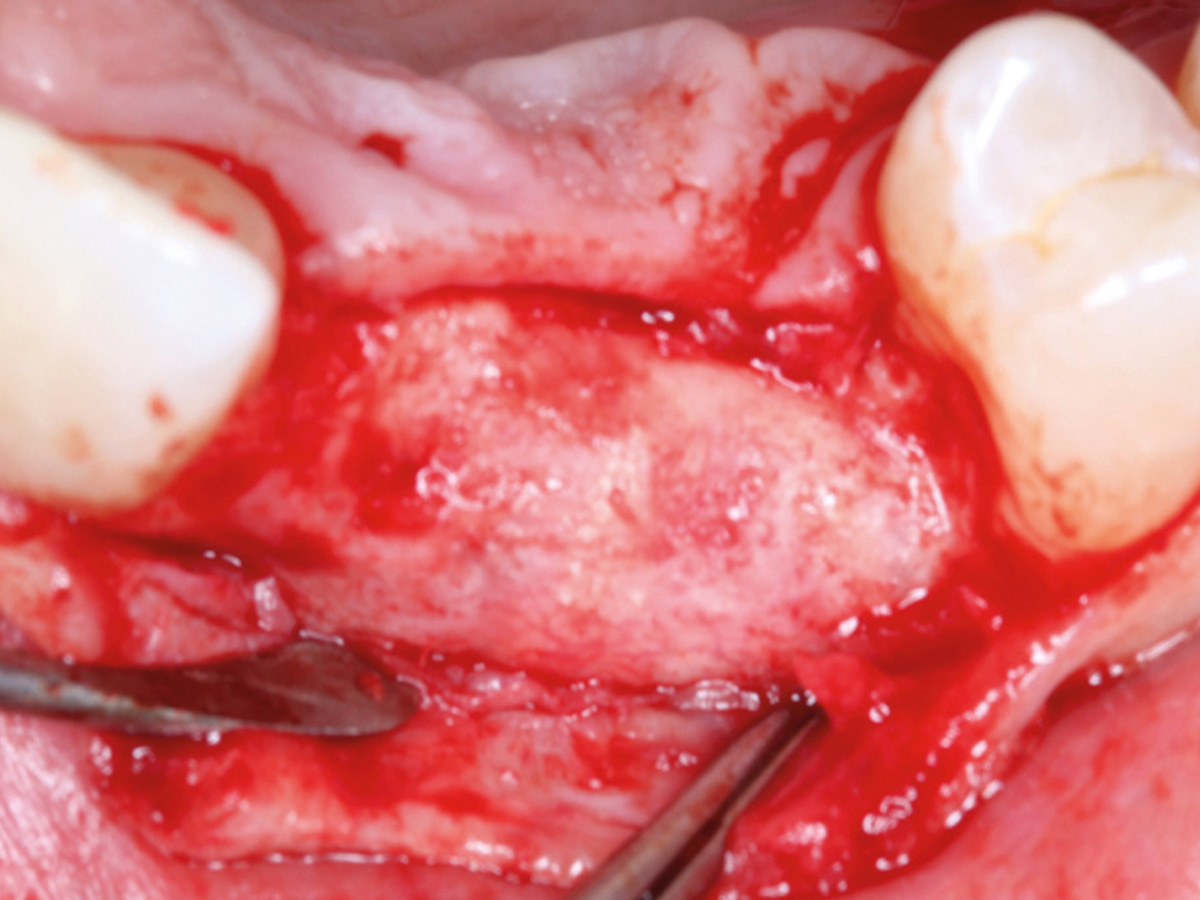

Abbildung 9

Retromolarer Eigenknochengewinn.